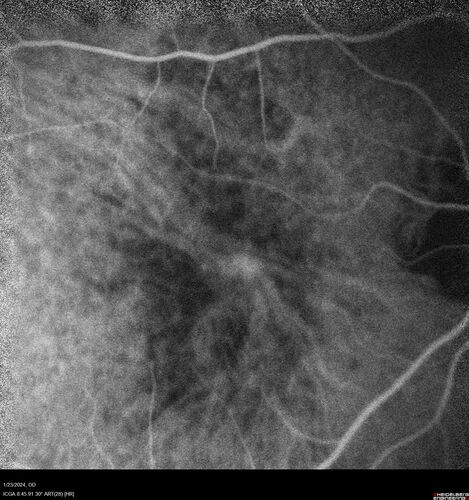

wet AMD with classic extrafoveal macular neovascularization in the good eye

89 year old man with longstanding vision loss in the left eye presented with one month of mild vision loss in the right eye.  Vision was 20/32.  This eye responded to vabysmo therapy.